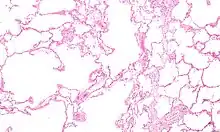

| Micrograph of an emphysematous lung; emphysema is a rare respiratory disease, strongly associated with smoking. H&E stain. | |

Asthma, chronic bronchitis, bronchiectasis and chronic obstructive pulmonary disease (COPD) are all obstructive lung diseases characterised by airway obstruction. This limits the amount of air that is able to enter alveoli because of constriction of the bronchial tree, due to inflammation. Obstructive lung diseases are often identified because of symptoms and diagnosed with pulmonary function tests such as spirometry. Many obstructive lung diseases are managed by avoiding triggers (such as dust mites or smoking), with symptom control such as bronchodilators, and with suppression of inflammation (such as through corticosteroids) in severe cases. One common cause of COPD including emphysema, and chronic bronchitis, is tobacco smoking, and common causes of bronchiectasis include severe infections and cystic fibrosis. The definitive cause of asthma is not yet known.[4]